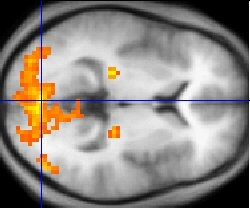

Как реагирует на благозвучные и неблагозвучные сочетания тонов головной мозг?

Его изображения, полученные с помощью позитронно-эмиссионной томографии во

время прослушивания испытуемыми созвучий-консонансов и диссонансов, показали,

что в развитии эмоциональных реакций участвуют различные области.

Аккорды-консонансы активизировали орбитофронтальную область коры (часть

мозговой системы вознаграждения) правого полушария, а также часть области,

расположенной под мозолистым телом. Аккорды-диссонансы вызывали активизацию

правой парагиппокампальной извилины. Таким образом, в развитии эмоциональных

переживаний, связанных с восприятием музыки, принимают участие две различные

системы мозговых структур. Ученые раскрыли еще одну тайну, связанную с

восприятием музыки. Когда они сканировали головной мозг музыкантов,

блаженствовавших во время прослушивания мелодий, они обнаружили, что звуки

вызывали активизацию ряда тех же самых мозговых систем вознаграждения,

которые активизируются и под влиянием вкусной еды, занятий сексом и приема

наркотиков.